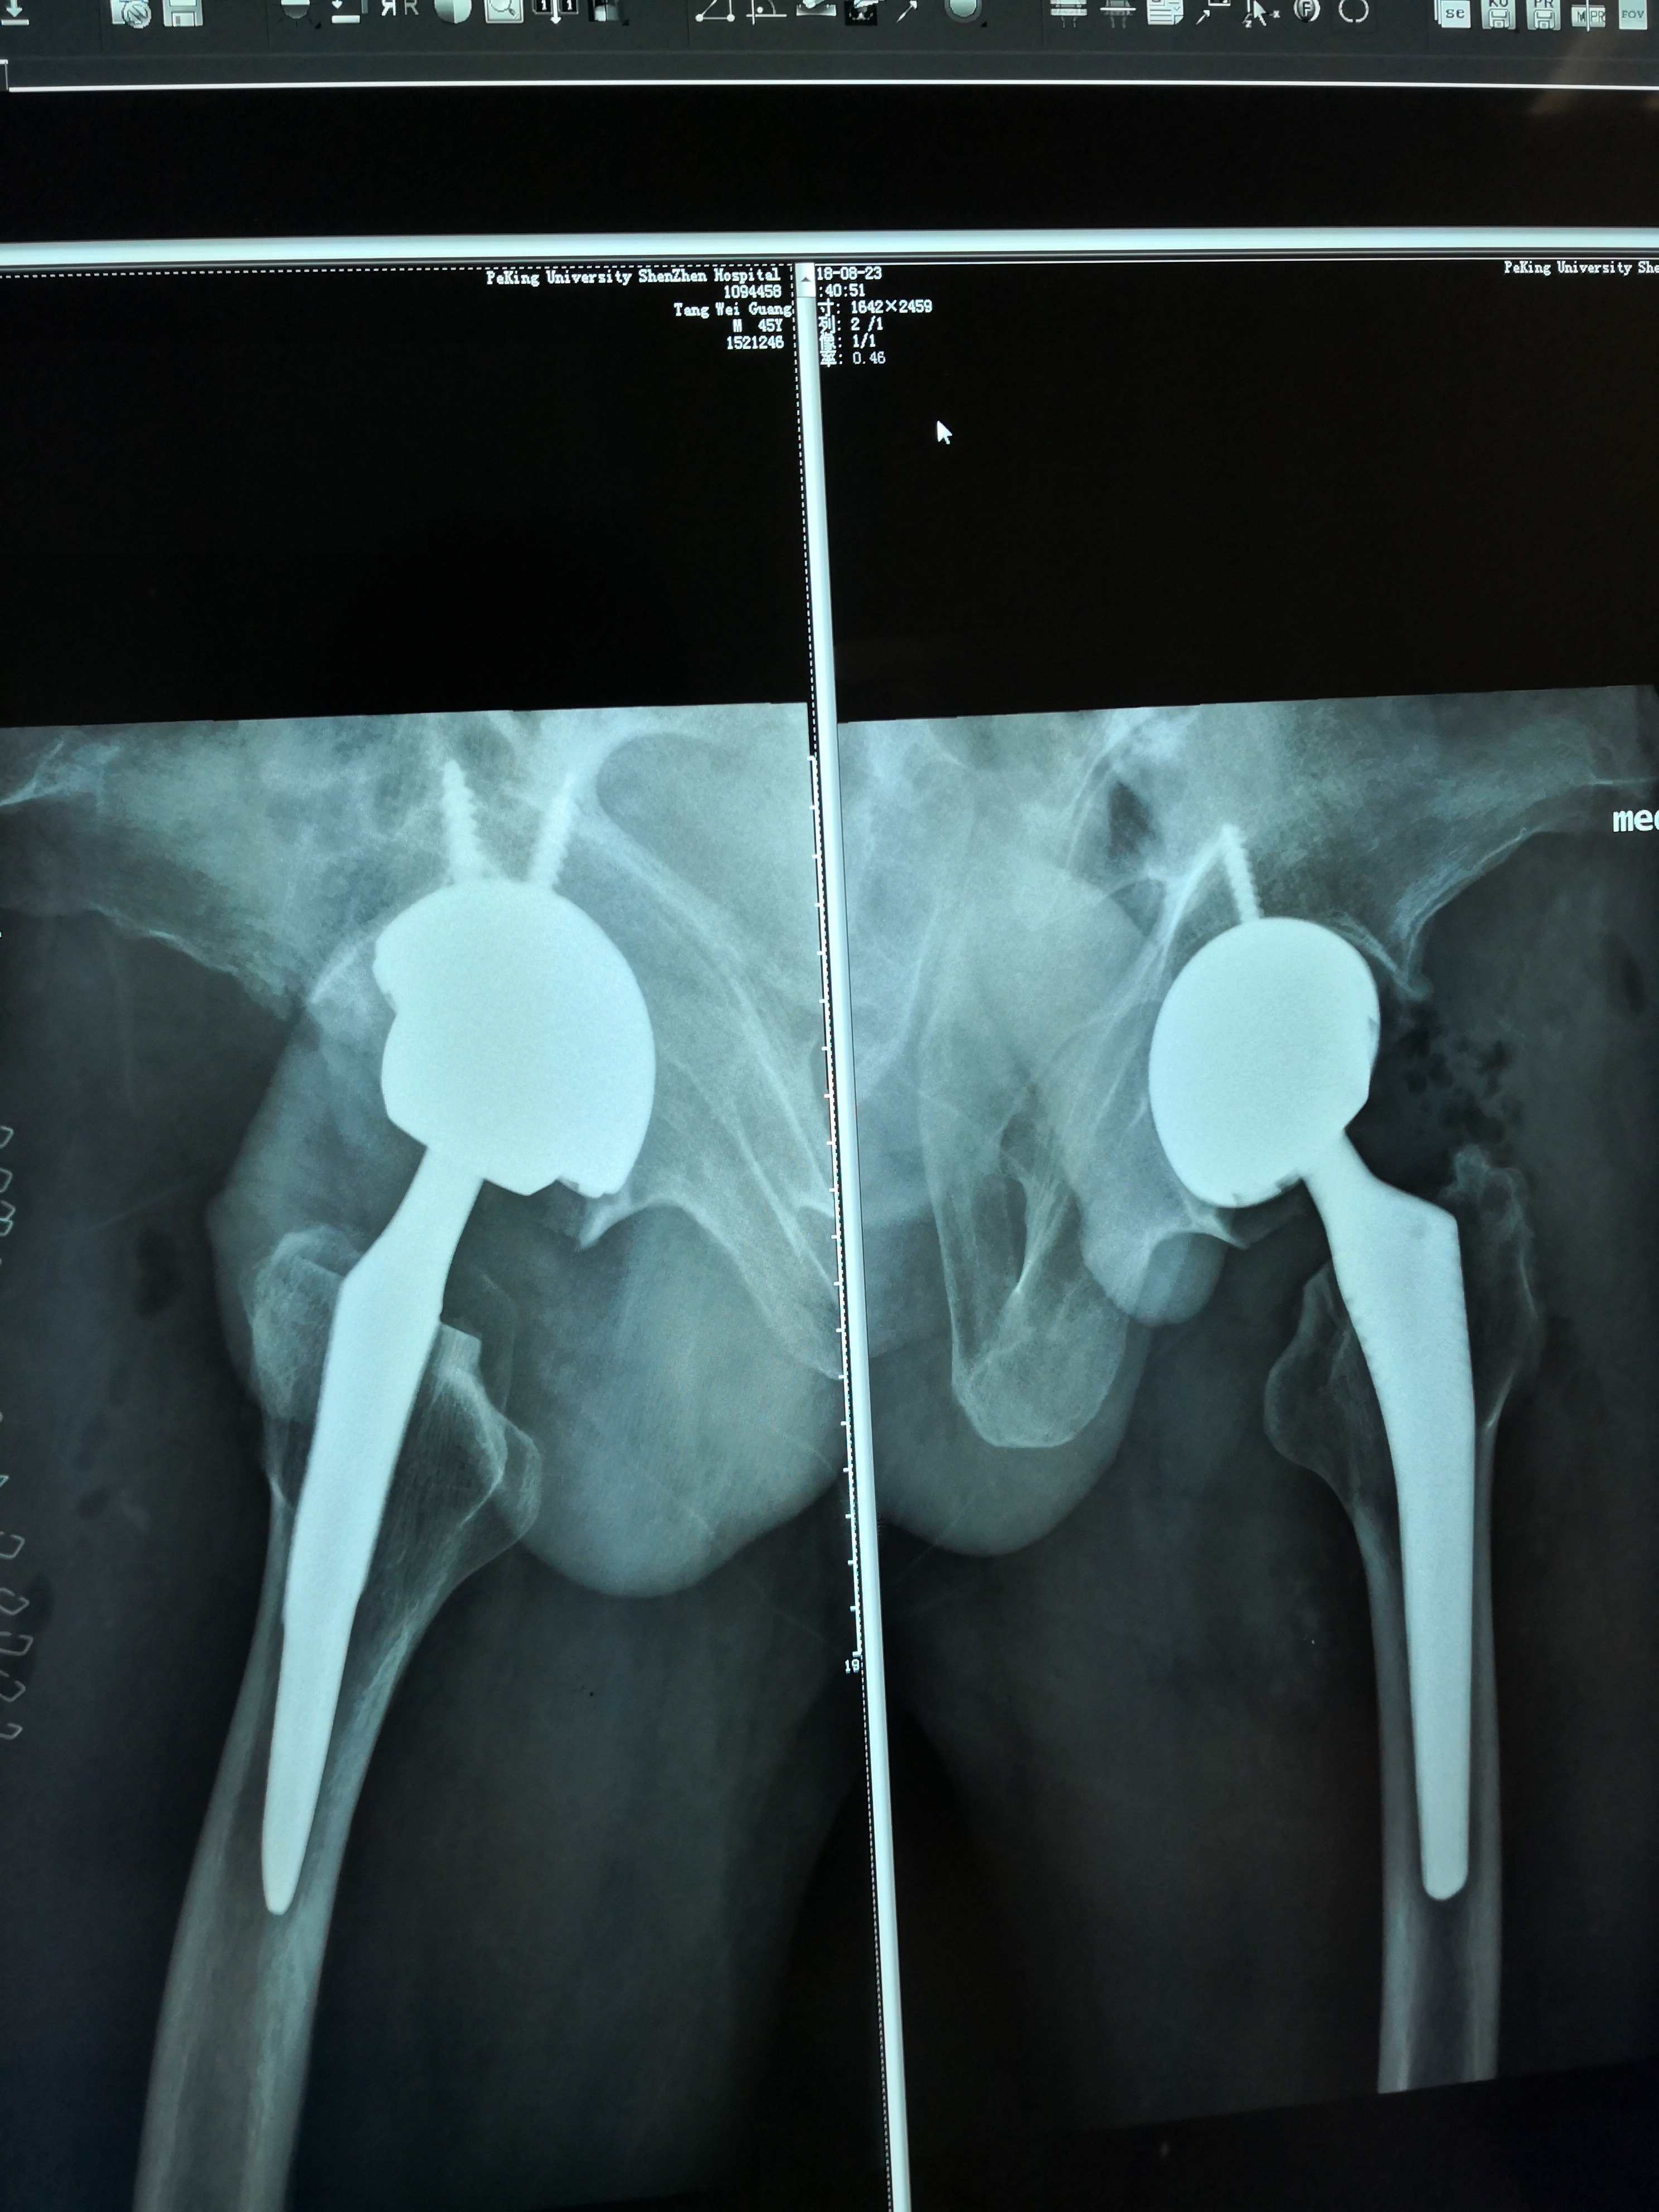

DAA入路治疗双侧股骨头坏死

患者中年男性,因双侧股骨头坏死导致行走疼痛多年。近期疼痛加重,双髋关节活动受限住院治疗。考虑患者中年男性,活动能力强。为了缩短康复时间,选用DAA入路一次性完成双侧髋关节置换手术。手术后患者恢复良好,术后三天就可以自由活动及正常下蹲。术后二周患者和正常人一样活动。术后有正常活动的视频,但无法发送到页面上。